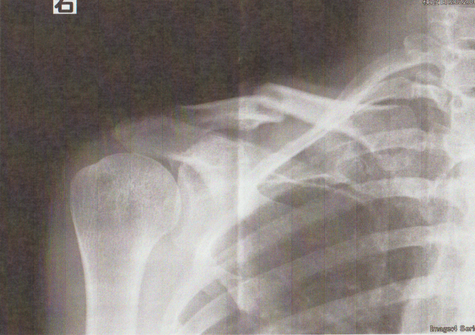

●右鎖骨骨折

当患者さんは手術療法に強く抵抗があり当院での保存療法を選択されました。

骨折部位の短縮転移があたので整復操作が必須になります。運よく短縮転移が矯正されたので保存療法で経過をみました。暑い時期だったので来院の度に固定を外し体を清拭して施術後、新しい下着の上から再度固定をする運びになりました。

骨折部位には超音波、患部以外の所は関節運動、経過を見て軽いマッサージを開始。固定も少しずつ簡易な物へ変更し二カ月後には三角巾のみ、三ヵ月経過すると肩関節の挙上もできるようになりました。

経過良好で完治しました。

左のレントゲンは短縮転位 (受傷時) 右は整復操作をして骨片が重なり合っている状態

整復後包帯と装具で固定。当初は週に2、3回来院してもらいその都度固定は取り外し、体を洗いました。

通常整形外科では取り外しも清拭もしないので暑い時期は患者様には試練です。ストレスは悪影響をもたらします。

局所には超音波治療を施し浮腫みのある指、肘はマサージににより軽減に努めました。6週ほど固定しましたが、各週ごとに固定を楽にしていくのでかなりストレスを軽減できたと思います。3か月目には肩を挙上できるまでになり、筋力強化運動により完治しました。